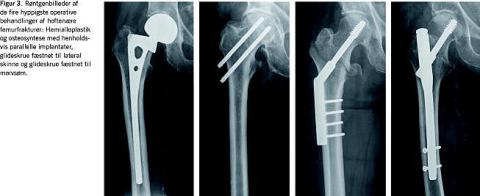

I Referenceprogrammet anbefales intern fiksering ved alle collumfrakturer, fraset hos patienter, der er over 75 år og har en disloceret collumfraktur, hvor der anbefales en hemialloplastik [1]. Gennemgangen af litteraturen gør det muligt at nuancere disse anbefalinger (Figur 1 og Figur 3 ). Således bør en alloplastik tillige overvejes ved den udislocerede fraktur med over 20° posterior frakturvinkling, hvor risikoen for komplikationer efter intern fiksering er øget [13]. For alloplastik taler også tilstedeværelsen af osteoporose eller artrose [1, 27]. For intern fiksation taler derimod anatomisk reposition og et stort caputfragment [26]. Osteosyntese bør også overvejes hos de ældste/demente patienter, som ikke forventes at kunne overholde bevægerestriktionerne ved en hemialloplastik, eller som dårligt tåler den større kirurgiske procedure herved [33]. Om calcar er intakt er dertil essentielt for valg af osteosyntesemetode [18, 27].

Den pertrokantære fraktur behandles hyppigst med reposition og intern fiksering med en glideskrue og lateral skinne fæstnet med 3-4 skruer i femurskaftet (Figur 2 og Figur 3). AVN ses sjældent. Frakturskred medfører dog reoperation hos 4-12%, afhængigt af frakturtype og operationsmetode [1, 8, 14-17, 35]. Frakturskred skyldes inadækvat reposition og placering af glideskruen, som inden for de første postoperative måneder kan medføre, at caputfragmentet dislocerer i varus, lateraliseres og/eller teleskoperes ned i femurmetafysen med risiko for glideskrueperforation af caput (cut-out ). Dette medfører smerte og forkortet benlængde.